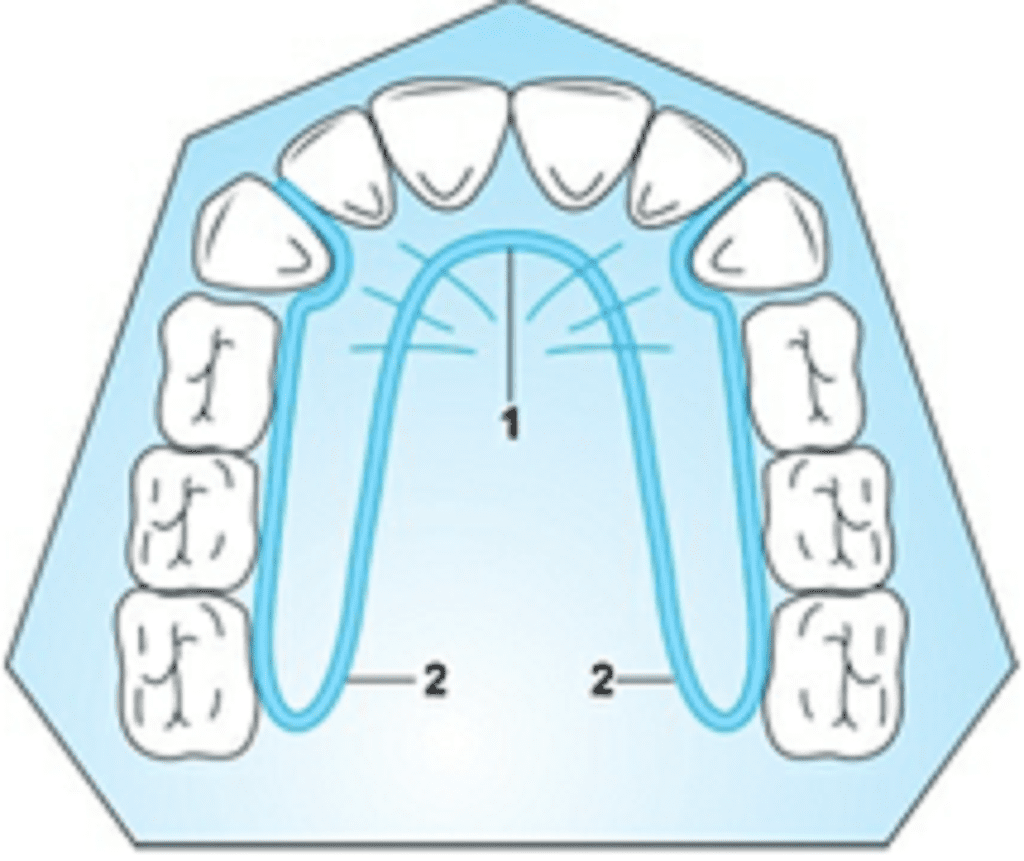

b) Coffin Spring

The coffin spring was introduced by Sir Walter Coffin in the year 1875.

This appliance is capable of producing slow expansion, even though it has been shown to split the palate especially when used in patients in the early mixed dentition

Appliance Framework Wire used: 1.25-mm heavy stainless steel wire. The appliance consists of an omega shaped wire, with the base of the omega placed posteriorly in the midline. The distal ends of the U loop are limited to the distal of the first permanent molar. Anteriorly, the loop gets constricted and recurved into the baseplate. Two separate acrylic wings are made around the wire framework on the slopes of the palate, these also contain the retentive clasps.

Activation Simply pulling the wings apart activates the appliance. This should be done first in the premolar region and then in the molar region. It can also be activated using three-prong pliers at the base of the omega, but are rarely used as they tend to distort the spring. Care must be taken to maintain the sides of the appliance in the same plane during adjustment.

Ideally, marking holes should be drilled on the two wings and a divider should be used to measure the amount of activation given. An expansion of 2–3 mm is made during activation.

Indications

- Expansion of constricted maxillary arch

- Correction of crossbite (unilateral cross bites)

- Conditions requiring differential expansion

Advantages

- Cheaper when compared to expansion screws

- Differential expansion of arch in the premolar or molar region is possible

- Less bulky

Disadvantage

Coffin spring tends to be unstable if it is not made precisely.